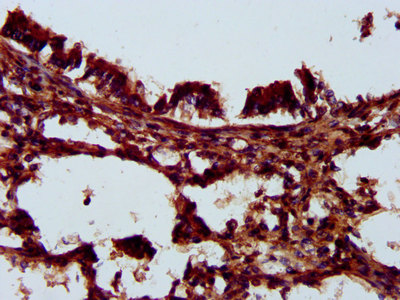

IHC image of CSB-PA868375LA01HU diluted at 1:200 and staining in paraffin-embedded human lung tissue performed on a Leica BondTM system. After dewaxing and hydration, antigen retrieval was mediated by high pressure in a citrate buffer (pH 6.0). Section was blocked with 10% normal goat serum 30min at RT. Then primary antibody (1% BSA) was incubated at 4°C overnight. The primary is detected by a biotinylated secondary antibody and visualized using an HRP conjugated SP system.